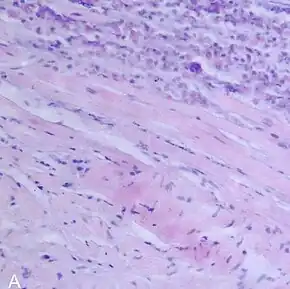

| A microscope image of myocarditis at autopsy in a person with acute onset of heart failure | |

The gold standard is the biopsy of the myocardium, in general done in the setting of angiography. A small tissue sample of the endocardium and myocardium is taken and investigated. The cause of the myocarditis can be only identified by a biopsy. Endomyocardial biopsy samples are assessed for histopathology (how the tissue looks like under the microscope): myocardial interstitium may show abundant edema and inflammatory infiltrate, rich in lymphocytes and macrophages. Focal destruction of myocytes explains the myocardial pump failure.[10] In addition samples may be assessed with immunohistochemistry to determine which types of immune cells are involved in the reaction and how they are distributed. Furthermore, PCR and/or RT-PCR may be performed to identify particular viruses. Finally, further diagnostic methods like microRNA assays and gene-expression profile may be performed.